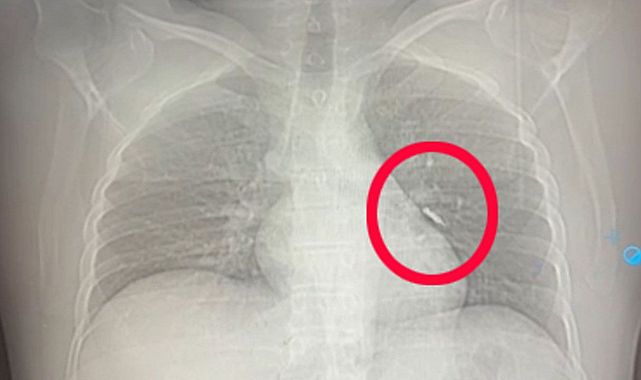

Van’ın İpekyolu ilçesinde implant tedavisi gören F.T. isimli hasta, tedavi sırasında implant vidasının yanlışlıkla soluk borusuna kaçmasıyla büyük tehlike atlattı. Vida, sol akciğerin üst lobundaki hava yollarına saplandı.

Göğüs Cerrahisi uzmanları Dr. Sadullah Aksoy ve Dr. Beniz İrem Ersoy Şığva tarafından yapılan bronkoskopi işlemiyle vida yerinden oynatıldı ancak tamamen çıkarılamadı. Müdahale yaklaşık 4 saat sürdü.